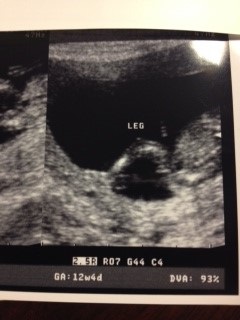

Hi ladies!! I had my 12w 4d u/s yesterday and I'm measuring 12w6d. I'm honestly not very good at the nub shot thing, so I'd love your guesses!!! I thought this would be the best picture to use, however I do have others if needed. Thanks so much!!!Attachment 15350